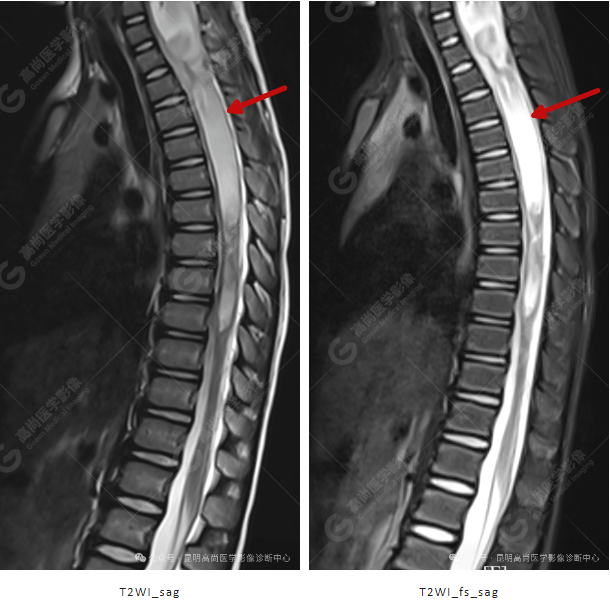

患者女,5 岁,出生时发现颈部包块,大小 3 cm×3 cm,5 年来无变化,拟行手术治疗,要求增强核磁协诊,否认体内金属物,无过敏史。

影像表现

颈 3-5 层面颈后部软组织不规则片状异常信号影,脊膜膨出可能;颈 3、4 棘突局部显示不清;颈胸髓内(约颈 3-胸 9 椎体水平)异常信号影,考虑囊肿并局部颈髓空洞可能,肿瘤或其他待排;请结合临床及相关检查。